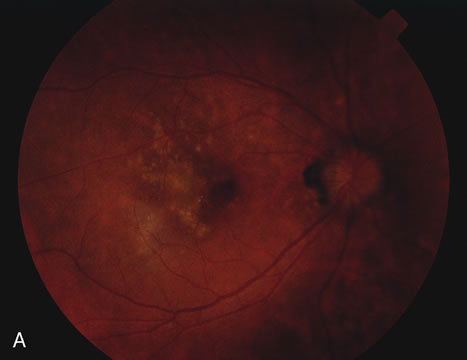

Determining whether the choroiditis has been caused by tuberculosis is sometimes very difficult. A chest x-ray may show evidence of an enlarged mediastinum as well as active pulmonary infiltrates or previous pulmonary scarring. Unfortunately, these are indirect evidence of ocular involvement or even that the disease is caused by tuberculosis. Sarcoidosis, histoplasmosis, and coccidiodomycosis can all give similar roentgenologic findings and somewhat similar fundus findings (Fig. 12).56 A long, thin, conjunctival biopsy measuring approximately 3 × 10 mm that is then sectioned in a breadloaf fashion can sometimes diagnose the presence of sarcoidosis.53 Mediastinoscopy or bronchoscopy can be used to determine the cause of the infiltrations. A purified protein derivative test (PPD) is done to see if there is a delayed hypersensitivity reaction indicative of exposure to tuberculosis. The PPD test may be positive in the absence of active tuberculosis. Unfortunately, outside the United States, bacille Calmette-Guérin (BCG) vaccine is given to try to decrease the incidence of tuberculosis. BCG can produce a false-positive PPD test. The polymerase chain reaction tests for tuberculosis are improving and can be considered if there is evidence that the laboratory where it will be performed has substantial experience in running this test. Vitreous or aqueous samples may be used if there is evidence of a vitreitis. In some cases a chorioretinal biopsy may be performed with the sample sent for tuberculosis culture, histopathology, and polymerase chain reaction.57 A response to antitubercular medications helps to make the diagnosis.58

Fig. 12. Multiple peripheral choroidal scars in an elderly patient with sarcoid uveitis. Note the resemblance to multifocal choroditis and also it can resemble intraocular lymphoma.

Non-Hodgkin's large cell lymphoma may present in many ways including a placoid pattern or a serpiginous choroiditis pattern (Fig. 13). It may also have a multifocal choroiditis pattern or present as MEWDS as well.59,60 Interleukin levels, flow cytometry, and histology are helpful in making the diagnosis. Sometimes Epstein-Barr virus stimulates the development of the non-Hodgkin's lymphoma and in situ hybridization will help demonstrate this.59

Fig. 13. Solitary choroidal lesion caused by large cell lymphoma.

Histoplasmosis and sarcoidosis are the most common differential diagnoses in a case of multifocal choroiditis. The cases of presumed ocular histoplasmosis do not have visual field defects or visual loss unless there is a choroidal neovascular membrane. Subretinal fibrosis is rare in cases of histoplasmosis and vitreous cells are also not present. Older patients, especially older white women, in their 60s and 70s may develop a form of sarcoidosis that looks like multifocal choroiditis. The lesions tend to be more often visible in the mid and far periphery than in the posterior pole and cystoid macular edema tends to be common.53